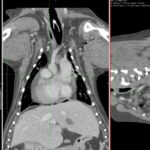

9歳の柴犬が散歩中に突然倒れる事があるとのことでかかりつけを受診しました。幼少時よりてんかん発作を発症する事があるが、今回の様子はてんかんの時とは異なる様だとのことで精査を希望され来院しました。心音は微弱でマッフルを呈していました。また、腹水の貯留も確認されました。心臓超音波検査では心膜液の貯留が確認されました。心嚢水の除去を行なったところ、出血性の心嚢水でした。数日間は心嚢水の除去のみで一般状態は改善していました。しかし、再発すると虚脱するといった症状が確認されたため、再発性の心タンポナーゼを回避するために、胸腔鏡下で心膜切除術を実施しました。同時に中皮腫、血管肉腫、特発性との鑑別にCTによる精査も実施しております。心膜の病理検査では腫瘍性の変化はなく、著しく繊維化した心膜であり、特発性と診断されました。胸腔鏡下での手術であったため、数日間の入院で痛みも少なく良好に経過しています。